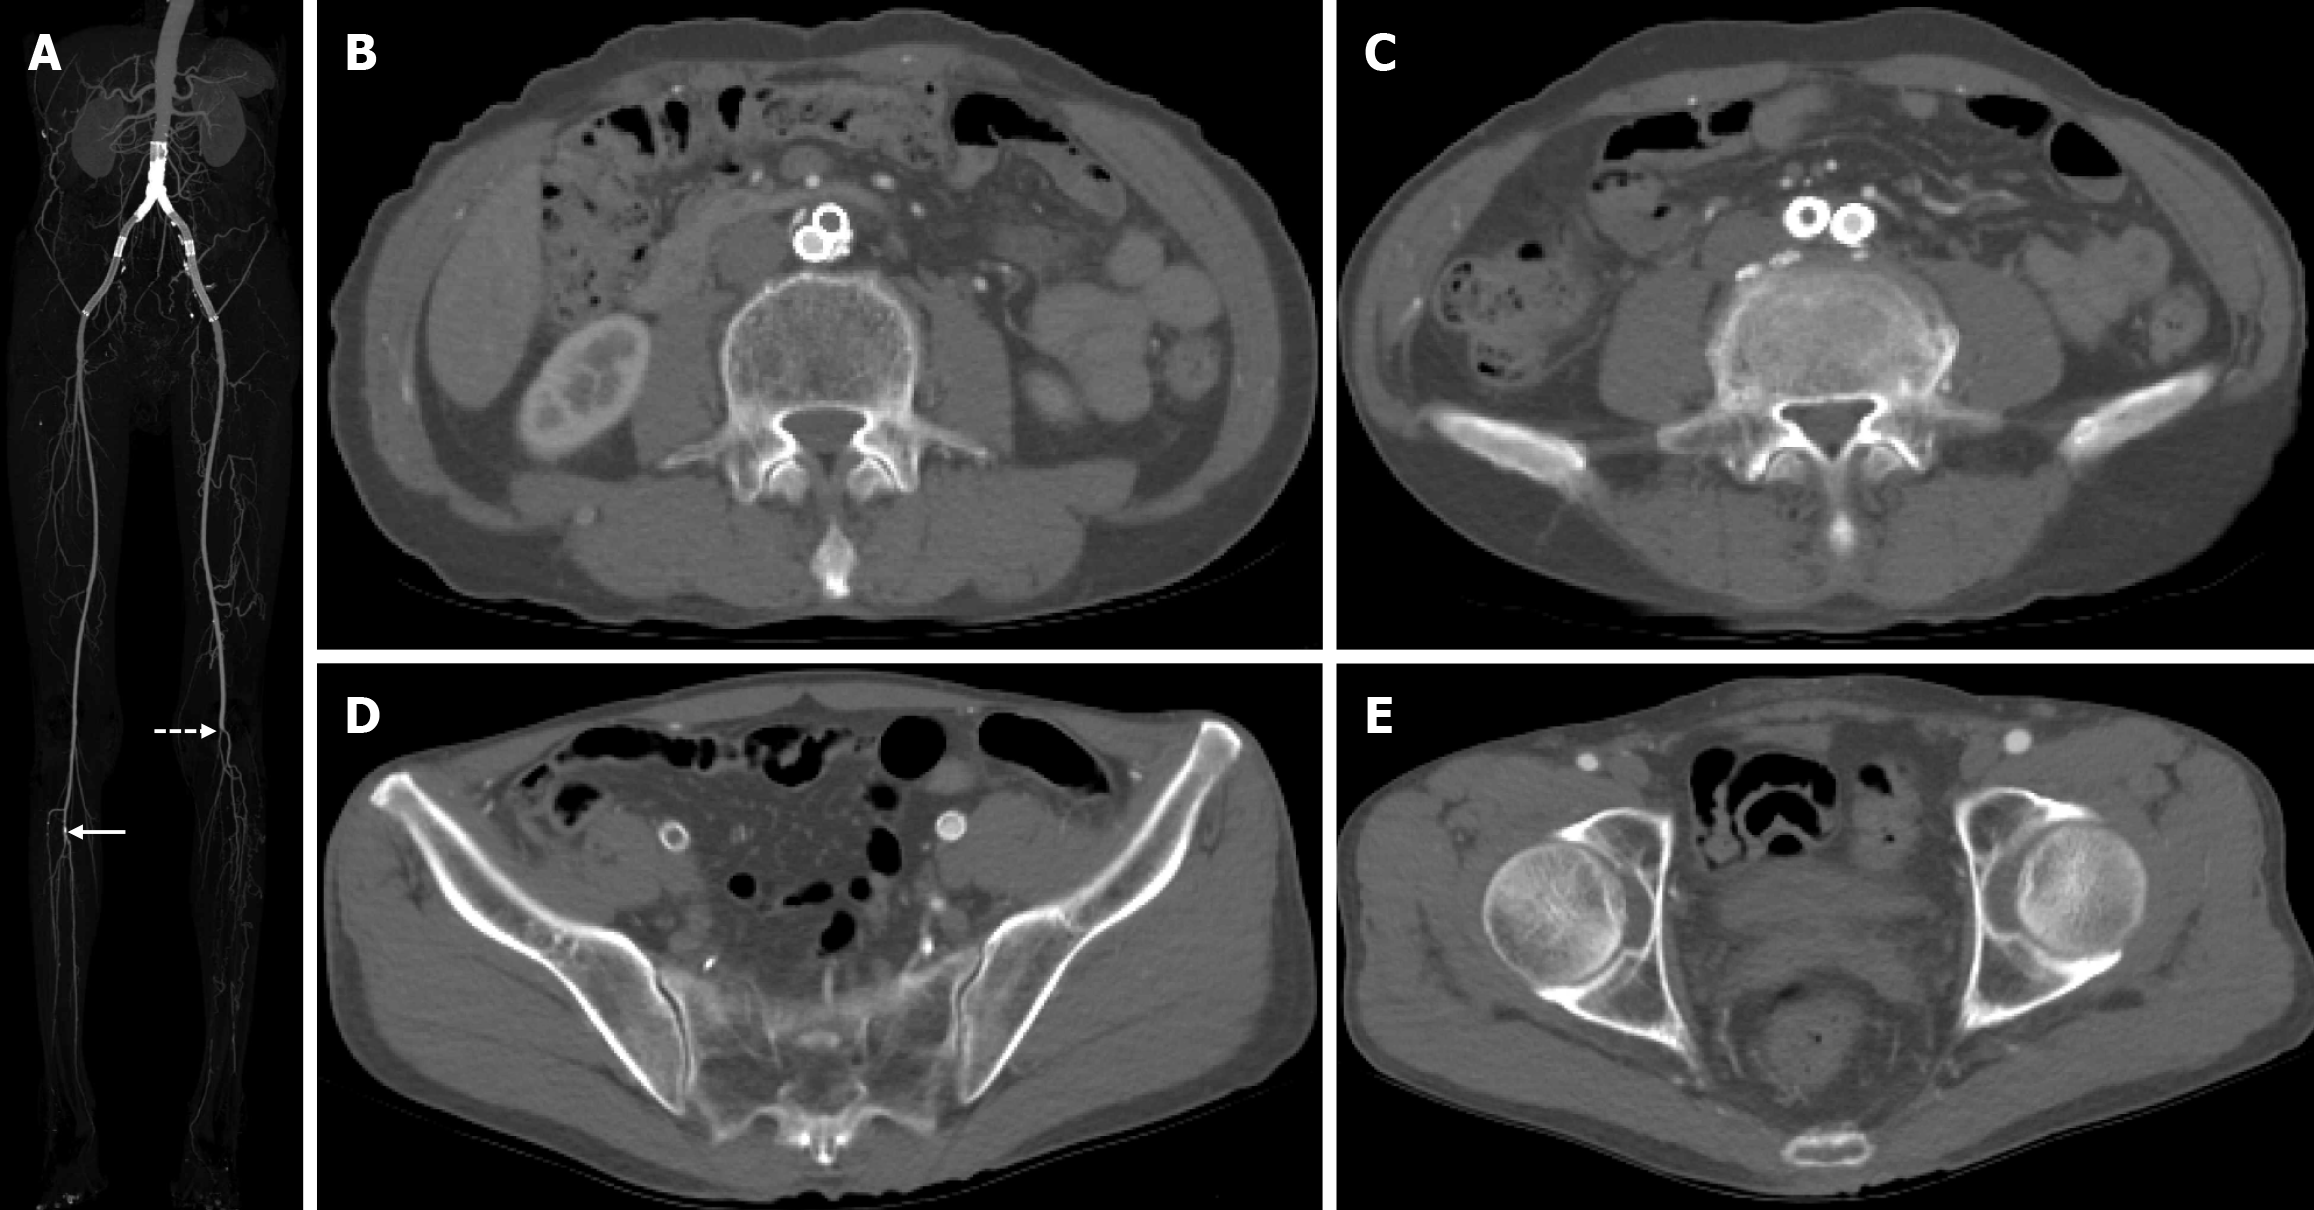

Contrast-enhanced lower extremity computed tomography (CT) revealed thrombotic occlusion of the right aortoiliac stent. The maximal intensity projection (MIP) image demonstrated the aorto-iliac stent placement, mild calcification of the right tibioperoneal trunk, and occlusion of the left popliteal and tibioperoneal arteries (Figure 1A). Serial axial section images showed the thrombotic occlusion of the right aortoiliac stent from the level of the abdominal aorta and right external iliac artery (Figure 1B-E).

The final diagnosis was a thrombotic occlusion of right aortoiliac stenting, mild calcification of right popliteal artery, and complete occlusion of left popliteal and tibioperoneal artery.